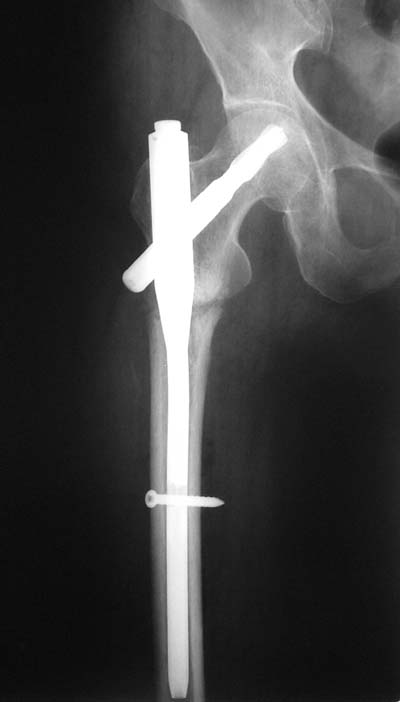

Да? Качество рентгенограмм конечно неочень, но ведь это нестабильный перелом 31.А2.2, не так ли?

Не думаю так. см вложение.